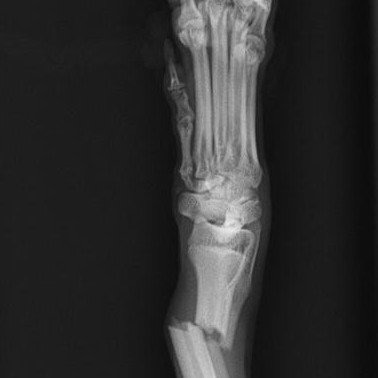

症例報告 橈尺骨骨折 手の骨折 シリウス犬猫病院

トイプードルやポメラニアン イタリアングレイハウンドなどの橈尺骨骨折 藤井寺動物病院 病院日誌

犬の橈尺骨骨折 動物別症例集 動物病院うみとそら 杉並区永福町 浜田山 方南町 高円寺 中野 世田谷